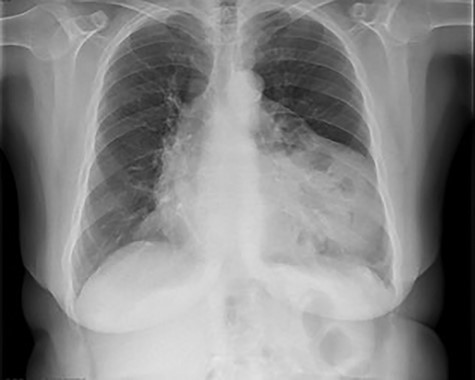

She had a chest X-ray done (Fig. 1) that showed widening of the mediastinum, as well as a few air-fluid levels, which raised suspicion of a diaphragmatic hernia. She also had a thoracic CT done (Fig. 2) that revealed a large hernia in the anterior mediastinum, containing transverse colon and a significant amount of ‘omentum,’ causing right side heart deviation.

Chest X-ray showing widening of the mediastinum and a few air-fluid levels